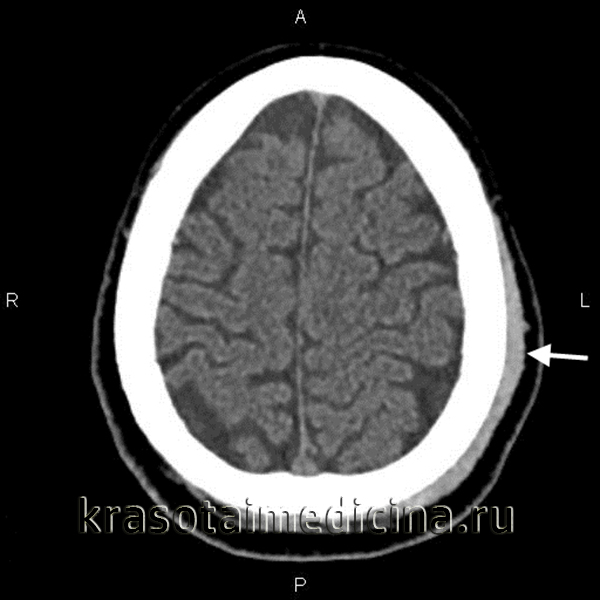

- КТ головного мозга. Как правило, на томограммах внутримозговая гематома имеет вид очага гомогенной плотности округлой или овальной формы. Если гематома сформировалась в результате ушиба головного мозга, то она обычно имеет неровный контур. С течением времени происходит уменьшение плотности гематомы до изоплотного состояния, при котором ее плотность соответствует плотности мозговой ткани. Для малых гематом этот период составляет 2-3 недели, а для средних — до 5 недель.

На сегодняшний день клиническая неврология использует несколько классификаций внутримозговых гематом, дающих представление о их различных характеристиках: расположении, размерах, этиологии. В зависимости от локализации выделяют центральную, субкортикальную и кортико-субкортикальную внутримозговую гематому, а также гематому мозжечка. Различают лобарные, медиальные, латеральные и смешанные внутримозговые гематомы. По размеру внутримозговая гематома может классифицироваться как:

- малая (до 20 мл, диаметр по КТ не более 3 см)

- средняя (20-50 мл, КТ-диаметр 3-4,5 см)

- большая (>50 мл, КТ-диаметр >4,5 см).